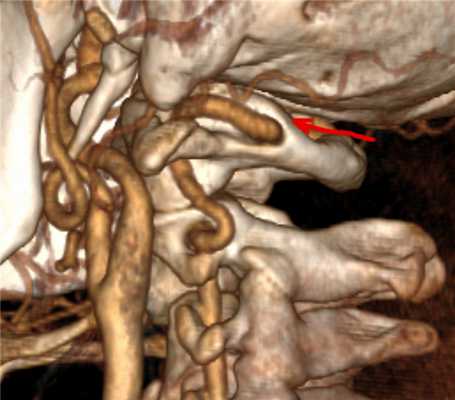

Компьютерная томография

Компьютерная томография с ангиографией (КТА) позволяет получить изображения позвоночных артерий без рисков, связанных с обычной ангиографией. Положительным свойством этого исследования является возможность трехмерной оценки поражений артерий на шейном и внутримозговом уровне. Оцениваются все сосудистые бассейны. Возможность выявления различных вариантов нарушения проходимости, как внутрисосудистых поражений (атеросклеротические бляшки и расслоение), так и внешних влияний (сдавление костями, связками, мышцами).